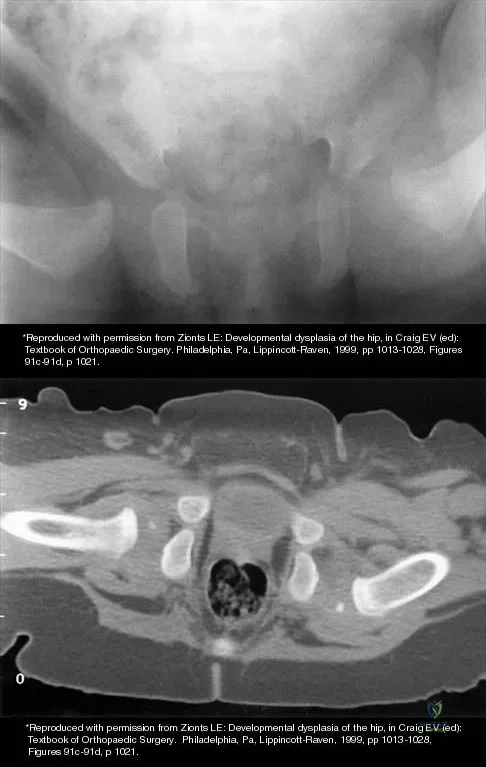

Question 55

The mother of a 3-month-old infant states that she has difficulty positioning the infant's legs during diaper changes. Examination reveals limited abduction of both hips and a negative Ortolani sign. A radiograph reveals bilaterally dislocated hips. Initial management consists of guided reduction in a Pavlik harness, with weekly follow-up. Figures 57a and 57b show the radiograph and CT scan obtained after 6 weeks in the harness. Management should now consist of

Explanation